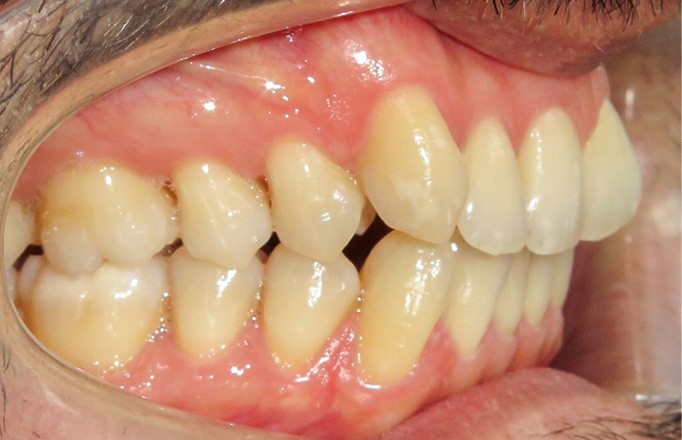

Discussion (fig. 5a- i)

La difficulté a été de garder le patient motivé, car les trois temps du traitement se sont ajoutés (2,5 ans) et le traitement reposait beaucoup sur sa coopération (dispositifs amovibles à savoir les élastiques et les gouttières).

Cependant, le patient est récompensé des choix qui ont été faits, car désormais son sourire est harmonieux avec une occlusion équilibrée. L’augmentation des triangles noirs a été limitée grâce aux soustractions amélaires au niveau des faces proximales des dents antérieures. En revanche, pour parfaire le résultat au niveau esthétique, des apports de composites ont été réalisés, car les dents de devant étaient très pincées au niveau cervical.

Le traitement est stable dans le temps, car les contacts occlusaux sont harmonieux ainsi que les fonctions et les déplacements ont été surtout coronaires.